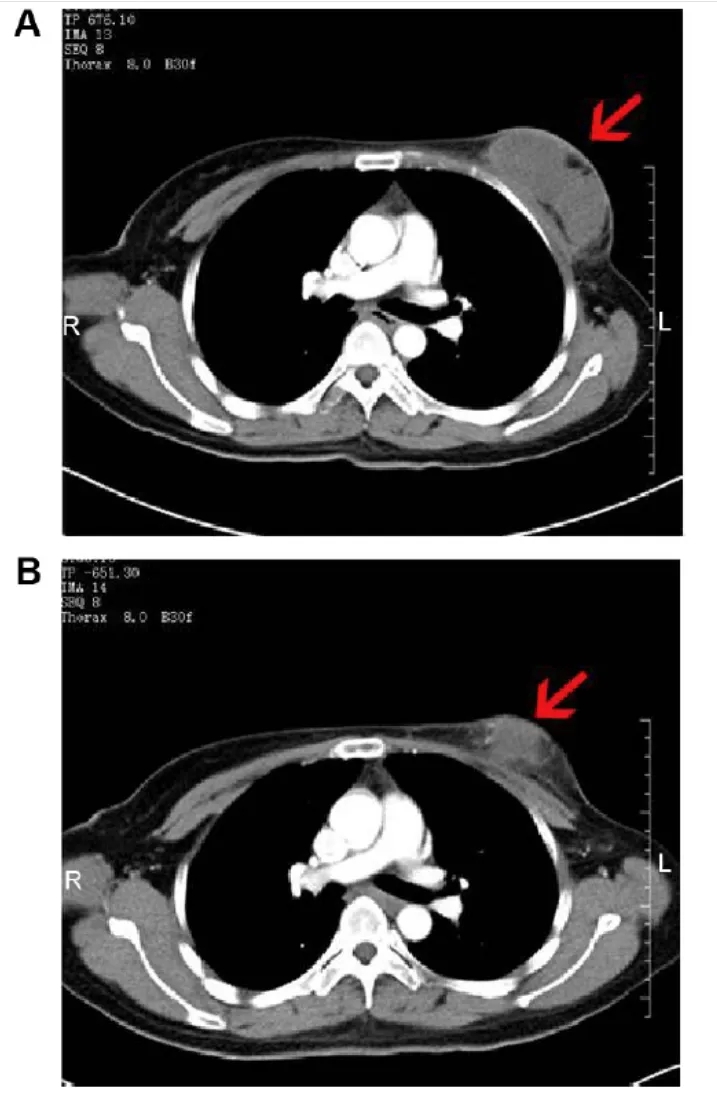

值得一提的是,其中一位46岁乳腺癌患者的疗效值得广泛关注。治疗前CT显示,其右乳存在8.0×3.8×5.7cm边界不清的软组织肿块(增强CT呈中度不均匀强化),腋窝有多处肿大淋巴结(较大者约2.9×1.7×3.8cm);接受NK细胞治疗2个月后,肿块缩小至6.8×3.5×5.8cm(呈轻度不均匀强化),较大肿大淋巴结亦明显缩小(详见下图)。

▲图源“Dovepress”,版权归原作者所有,如无意中侵犯了知识产权,请联系我们删除